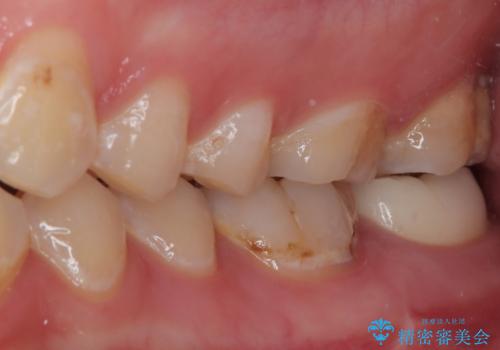

根管治療を行った歯は原則としてクラウンによる補綴治療が必要となるため、事前に親知らずを抜歯し、その後根管治療を行うこととしました。

根管治療後は状態を確認し、オールセラミッククラウンにて補綴治療を行うこととしました。